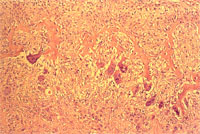

組織病變: 上、下顎之骨質明顯出現骨質過度被重吸收的病變,正常骨組織減少,排列疏鬆,而被大量纖維結締組織取代,而使原有正常結構消失(圖3)。此外尚可見多數多核巨細胞樣之蝕骨細胞雜夾於增生的纖維結締組織中(圖4)。